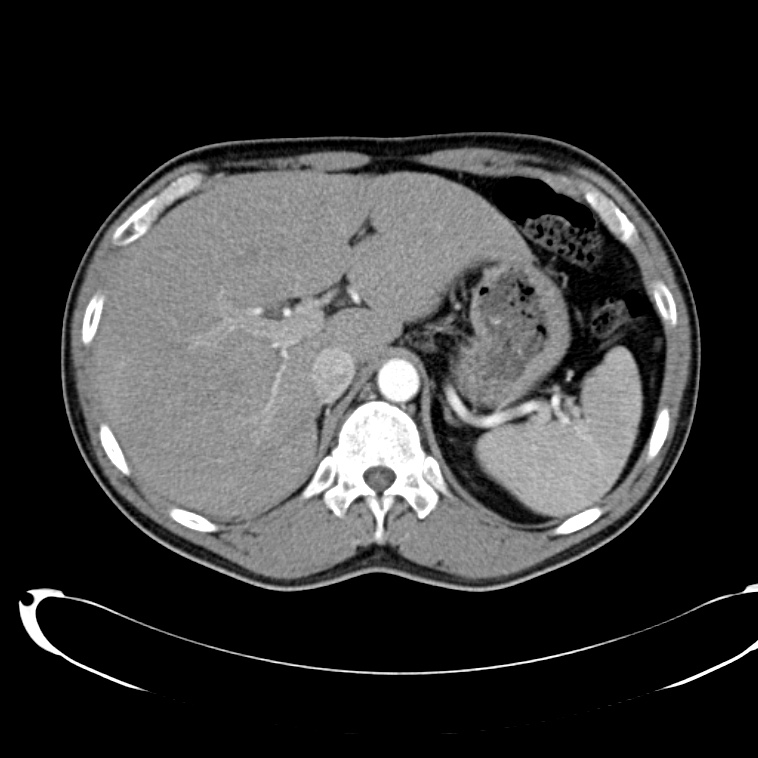

Ct Scan Abdominal . Viewing a ct scan, an experienced radiologist can diagnose many causes of abdominal pain or injury from trauma with very high accuracy. A ct scan can see nearly all parts of the body and is used to diagnose disease or injury as well as to plan medical, surgical or radiation treatment. Find out what to expect before, during, and after the procedure, and what risks and side effects it may have. A ct (computed tomography) scan is an imaging test that helps healthcare providers detect diseases and injuries. Learn what an abdominal ct scan is, how it works, and what conditions it can help diagnose. It uses a series of x. Abdominal ct scans are typically quick, lasting about ten minutes. Abdominal ct scans can help diagnose kidney ailments, such as kidney stones, kidney or ureter damage, polycystic kidney disease, or kidney. Diagnostics & testing / ct (computed tomography) scan. A provider might use contact dye depending on the rationale for ordering an abdominal ct scan. Abdominal ct scans are a diagnostic tool for identifying infections, inflammation, injury, or cancer in the abdomen or pelvis. What is a ct scan of the abdomen?